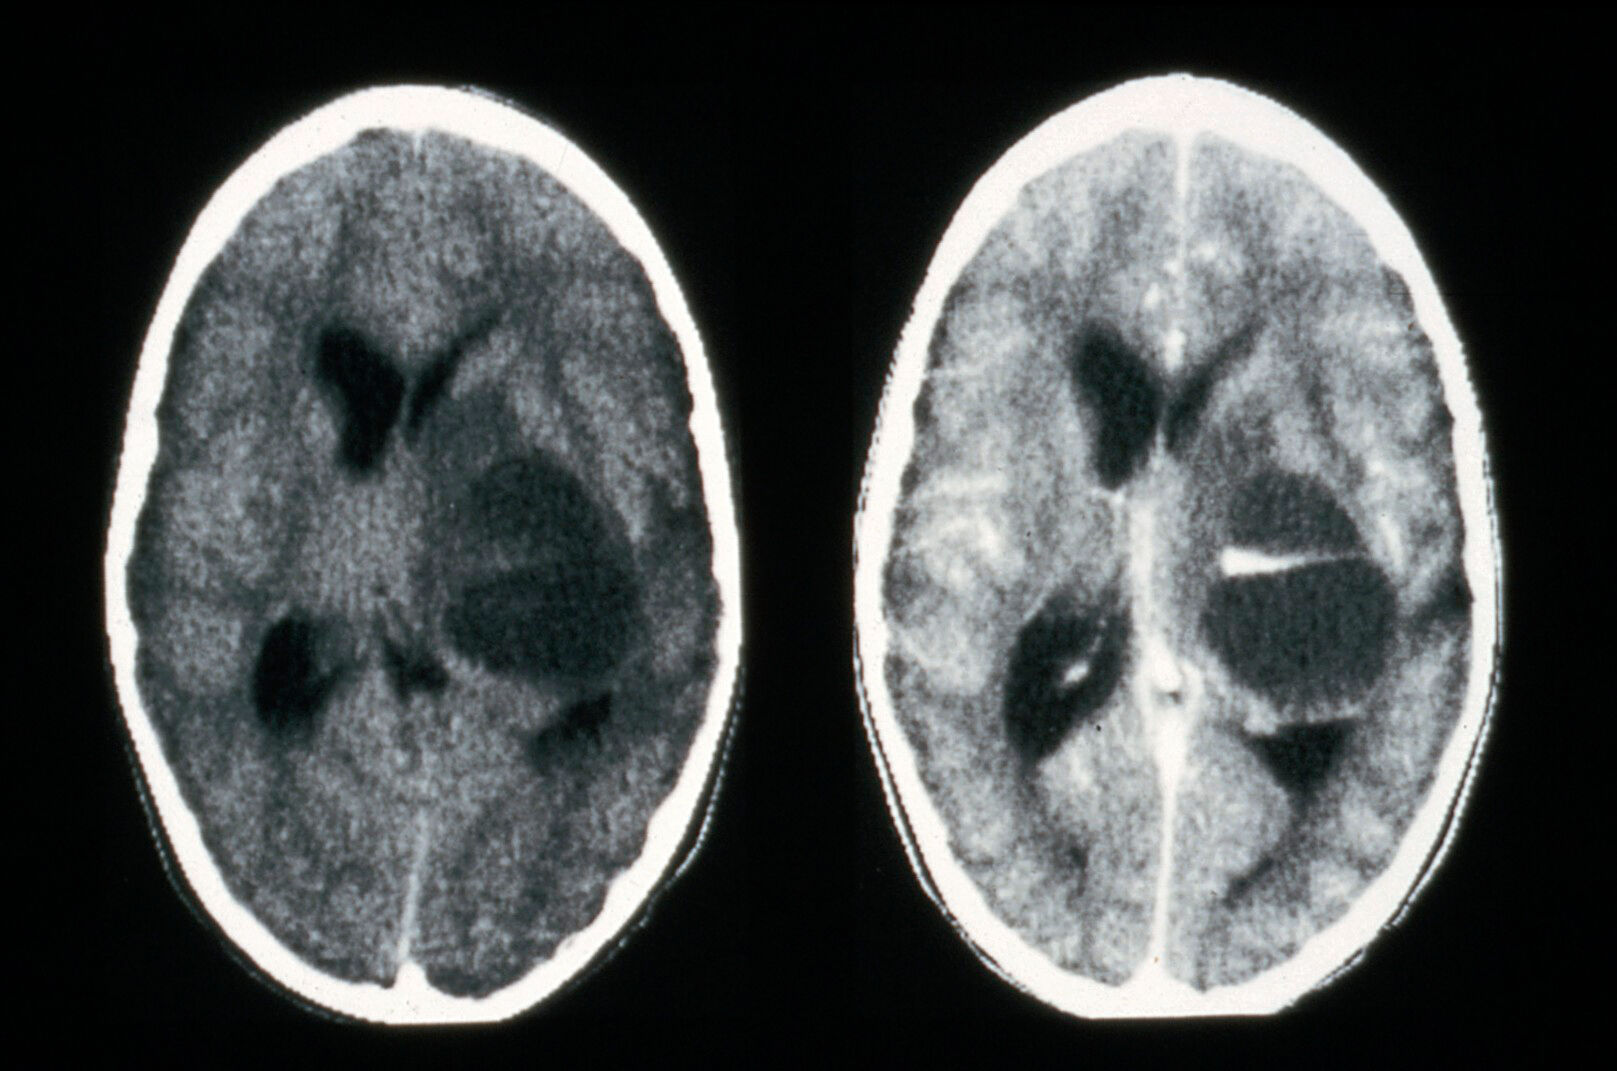

Brain Anatomy Ct Scan Images . when reading a brain computed tomography (ct), the left side of the image depicts the patient’s right side,. Ct brain by gourab mitro plaban. The cerebral cortex is a layer of grey matter formed in gyri (folds) over the entire brain surface. Citation, doi, disclosures and article data. Annotated teaching ct head in standard and bone windows. important grey matter structures visible on ct images of the brain include the cortex, insula, basal ganglia, and thalamus. This article lists a series of labeled imaging anatomy. this tutorial takes you through the important anatomy required to understand ct images of the brain. Hover on/off image to show/hide findings. Ct head by mohit kumar. 111 normal anatomy by mohamed shweel. 78 public playlists include this case.

Brain Anatomy Ct Scan Images when reading a brain computed tomography (ct), the left side of the image depicts the patient’s right side,. this tutorial takes you through the important anatomy required to understand ct images of the brain. 78 public playlists include this case. Hover on/off image to show/hide findings. Citation, doi, disclosures and article data. Ct brain by gourab mitro plaban. Ct head by mohit kumar. when reading a brain computed tomography (ct), the left side of the image depicts the patient’s right side,. important grey matter structures visible on ct images of the brain include the cortex, insula, basal ganglia, and thalamus. The cerebral cortex is a layer of grey matter formed in gyri (folds) over the entire brain surface. Annotated teaching ct head in standard and bone windows. This article lists a series of labeled imaging anatomy. 111 normal anatomy by mohamed shweel.